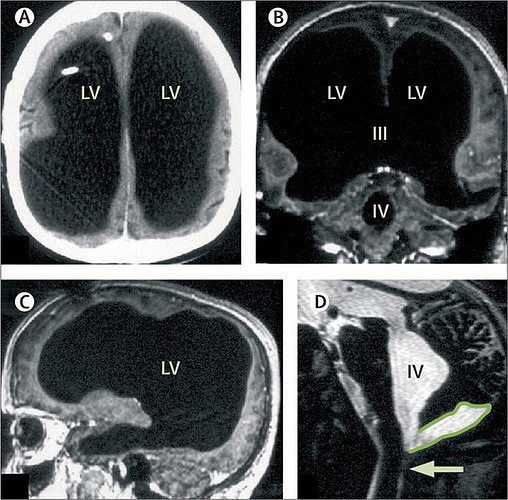

Ảnh chụp cho thấy người đàn ông này hầu như không có tí não nào. (Feuillet et al./The Lancet).

Trường hợp đặc biệt này được trình bày trên tờ Lancet, khiến những lý thuyết nền tảng khoa họccủa con người bị lung lay.

Theo MetroNews đưa tin, người đàn ông đã sống hoàn toàn bình thường trong 44 năm qua. Thậm chí, anh đã kết hôn, có 2 con trai, và làm việc trong cơ quan nhà nước và không hề bị hiện tượng rối loạn thần kinh.

Sau khi kiểm tra chỉ số IQ là 75, mặc dù hơi thấp so với mức trung bình nhưng cũng khiến các nhà khoa học vô cùng bối rối.

Nhà tâm lý học Axel Cleeremans từ Đại học Bruxelles (Bỉ) phải thốt lên rằng, “chẳng sách vở nào giải thích được tại sao một người mất 90% tế bào thần kinh lại hoàn toàn bình thường”.